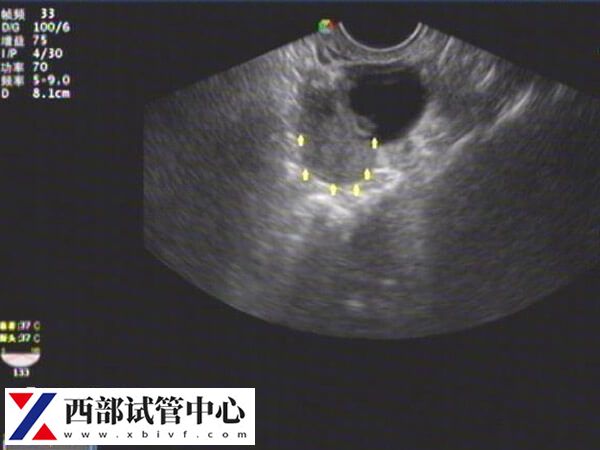

如果自然怀孕困难,可以考虑辅助生殖技术,如试管婴儿等。这些技术能够帮助患者提高怀孕几率,并增加成功受孕的可能性。通常会先检查评估患有残角子宫的人是否适合胚胎着床,如何适合可直接选择第三代试管婴儿,从而迎接好孕。